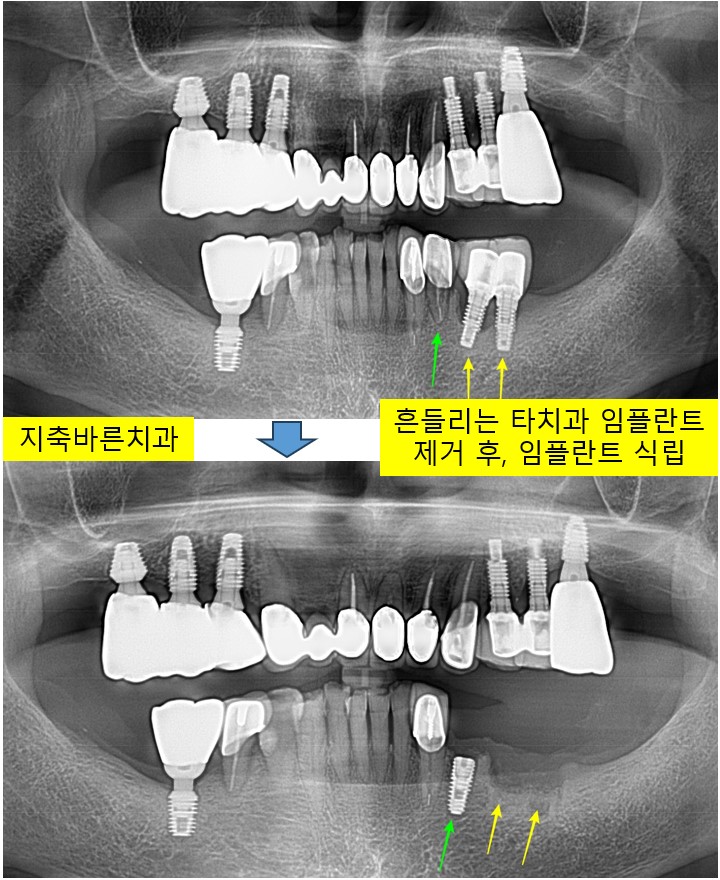

<흔들리는 타치과 임플란트 제거 후 임플란트 식립>지축치과 지축역치과 삼송치과 원흥치과 원당치과 화정치과 종로치과 파주치과 운정치과 대화치과 일산치과 일산임플란트 양주치과 미백 5

15년전 미국에서 식립한 왼쪽 아래 임플란트 2개가 많이 흔들리신다며 2024년 10월 80대 Kㅁㅁ 님께서 내...